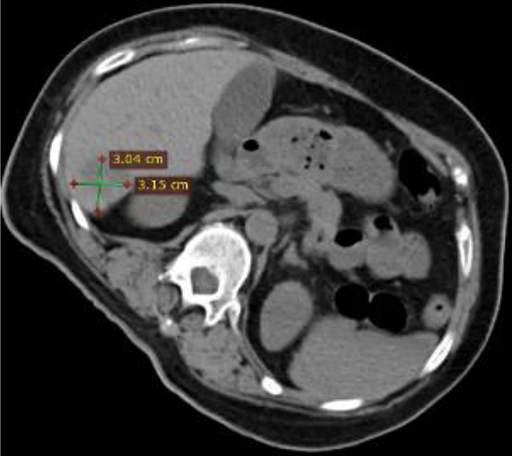

Ablation site with clear visible boundary on imaging